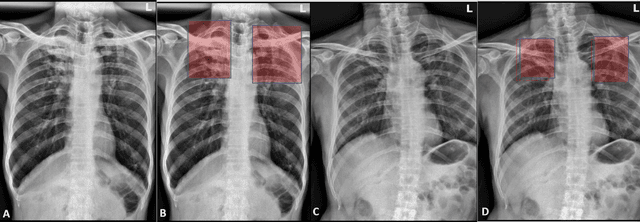

Abstract:Deep learning semantic segmentation algorithms can localise abnormalities or opacities from chest radiographs. However, the task of collecting and annotating training data is expensive and requires expertise which remains a bottleneck for algorithm performance. We investigate the effect of image augmentations on reducing the requirement of labelled data in the semantic segmentation of chest X-rays for pneumonia detection. We train fully convolutional network models on subsets of different sizes from the total training data. We apply a different image augmentation while training each model and compare it to the baseline trained on the entire dataset without augmentations. We find that rotate and mixup are the best augmentations amongst rotate, mixup, translate, gamma and horizontal flip, wherein they reduce the labelled data requirement by 70% while performing comparably to the baseline in terms of AUC and mean IoU in our experiments.